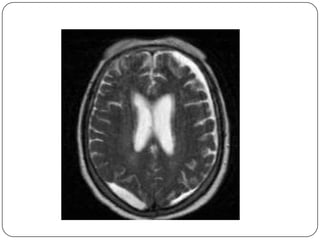

Imagen por Resonancia Magnetica Discordancia Clinica – radiologica  Evolucion torpida  Evaluacion de secuelas Valora mejor:  Hematomas pequenos  Lesiones de tallo y cuerpo calloso  Lesiones no hemorragicas Exploracion mas prolongada (20 30 m)

Ofrece una diferenciaciónentre la sustancia gris y la sustancia blanca todavía mayor que la TC. Permite la obtención de imágenes directas en los planos coronal y sagital. LCR aparece negro, aunque el hueso cortical se muestra negro, la grasa y cuero cabelludo son muy blancas.